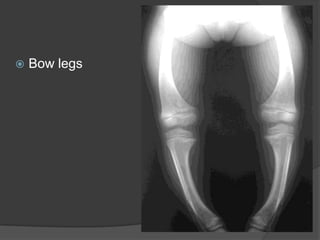

Bowed legs (genuvarum) in Toddlers

Valgus or varus deformities